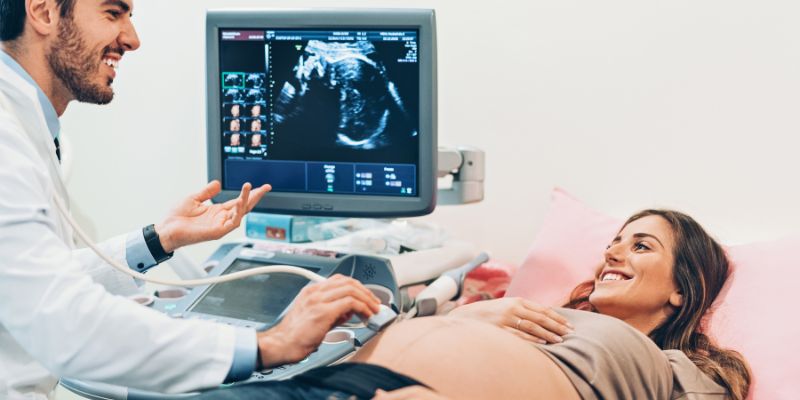

Siêu âm quét khi mang thai 16 tuần

Siêu âm ở tuần thứ 16 sẽ cho thấy sự trưởng thành của các cơ quan. Vị giác của bé sẽ hình thành và lông mày, tóc và lông mi của bé cũng vậy. Vì giờ đây em bé của bạn có thể xác định được giọng nói và âm thanh, điều đó cho thấy rằng các xương nhỏ của tai, cũng như màng nhĩ sẽ phát triển.

Ngoài siêu âm, bạn cũng có thể xét nghiệm nước tiểu trong tuần này để kiểm tra bệnh tiểu đường và các bệnh khác. Bên cạnh đó, các dấu hiệu thông thường về sự phát triển của bé như nhịp tim, các cơ quan đang trưởng thành, chuyển động và nhạy cảm với ánh sáng đều có thể được lập biểu đồ.